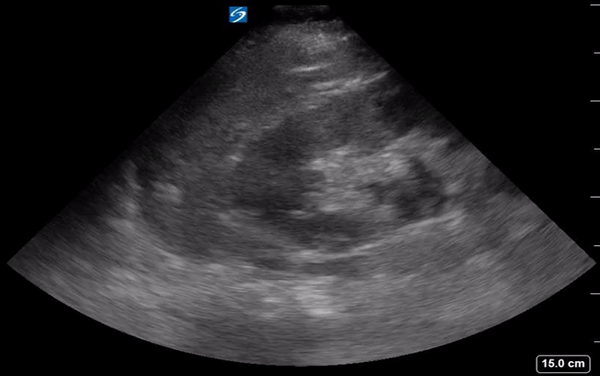

Clip 2: L kidney, + hydro

• POCUS renal on the right (Clip 1) without hydro. The left, however, shows hydro (Clip 2), raising suspicion for nephrolithiasis. CT non-con showed 4mm obstructing UVJ stone on the left.